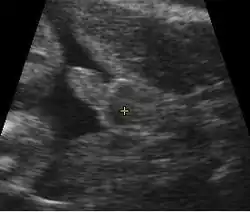

Early pregnancy

A gestational sac can be reliably seen on transvaginal ultrasound by 5 weeks' gestational age (approximately 3 weeks after ovulation). The embryo should be seen by the time the gestational sac measures 25 mm, about five and a half weeks.[10] The heartbeat is usually seen on transvaginal ultrasound by the time the embryo measures 5 mm, but may not be visible until the embryo reaches 19 mm, around 7 weeks' gestational age.[5][11][12] Coincidentally, most miscarriages also happen by 7 weeks' gestation. The rate of miscarriage, especially threatened miscarriage, drops significantly after normal heartbeat is detected, and after 13 weeks.[13]

Contents in the cavity of the uterus seen at approximately 5 weeks of gestational age -

Artificially colored, showing gestational sac, yolk sac and embryo (measuring 3 mm as the distance between the + signs) -

Embryo at 5 weeks and 1 day of gestational age (at top left) with discernible heartbeat -

Embryo at 5 weeks and 5 days of gestational age with discernible heartbeat